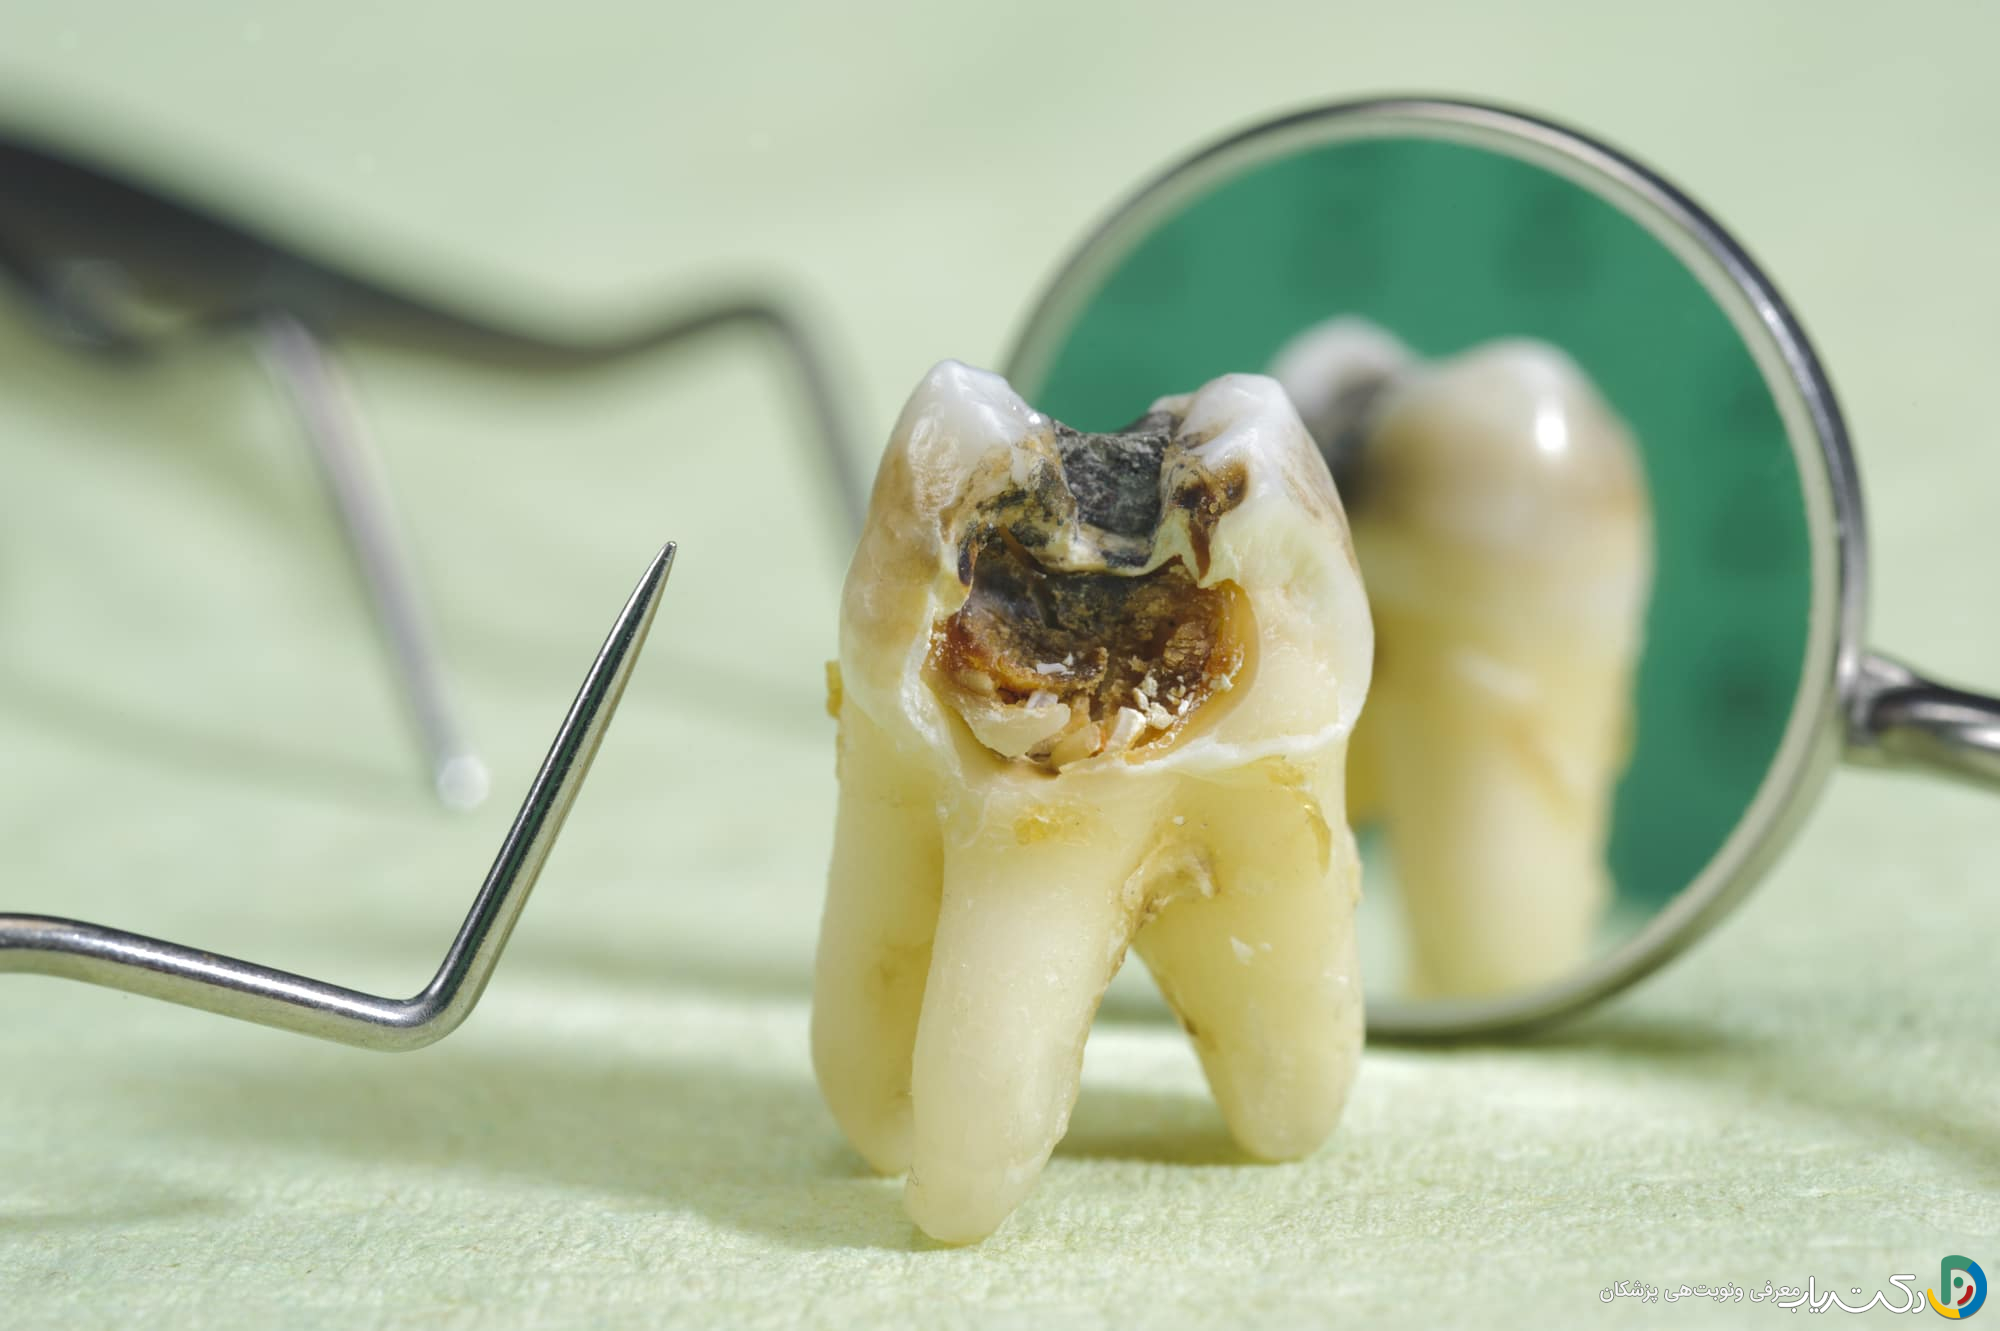

مرحله دوم: تخریب مینای دندان

اگر فرآیند معدنی‌زدایی ادامه یابد، ساختار مینا ضعیف‌تر شده و سطح خارجی آن فرو می‌ریزد و یک حفره کوچک ایجاد می‌شود. لکه سفید ممکن است به رنگ قهوه‌ای یا سیاه تغییر کند. در این مرحله، آسیب دائمی است و دندان نیاز به ترمیم (پر کردن) توسط دندانپزشک دارد. حساسیت خفیف ممکن است شروع شود.

مرحله سوم: پوسیدگی عاج (Dentin)

عاج، لایه‌ای زرد رنگ و نرم‌تر در زیر مینا است که حاوی هزاران لوله میکروسکوپی (توبول) است که مستقیماً به عصب دندان متصل هستند. وقتی پوسیدگی به عاج می‌رسد، به دلیل نرمی بیشتر، با سرعت بیشتری پیشرفت می‌کند. در این مرحله، حساسیت دندانی به محرک‌های سرد، گرم و شیرین به یک علامت شایع تبدیل می‌شود، زیرا این محرک‌ها از طریق توبول‌ها به عصب می‌رسند.

مرحله چهارم: درگیری پالپ (Pulp)

پالپ، بخش زنده‌ی دندان است که حاوی اعصاب، عروق خونی و بافت همبند می‌باشد. وقتی باکتری‌ها به پالپ نفوذ می‌کنند، باعث التهاب و عفونت آن می‌شوند (پالپیت). این وضعیت منجر به دردهای شدید، خودبه‌خودی، ضربان‌دار و طولانی‌مدت می‌شود که ممکن است با دراز کشیدن تشدید شده و فرد را از خواب بیدار کند. در این مرحله، درمان ریشه (عصب‌کشی) برای نجات دندان ضروری است.

مرحله پنجم: تشکیل آبسه (Abscess)

اگر عفونت پالپ درمان نشود، پالپ می‌میرد (نکروز می‌شود) و عفونت از طریق نوک ریشه به استخوان فک گسترش می‌یابد. این امر منجر به تشکیل یک کیسه پر از چرک به نام آبسه پری‌آپیکال می‌شود. علائم آبسه شامل درد شدید هنگام جویدن، تورم لثه و صورت، طعم بد در دهان و گاهی تب و بی‌حالی عمومی است. آبسه یک وضعیت اورژانسی است که نیاز به درمان فوری دارد، زیرا عفونت می‌تواند به سایر نقاط بدن سرایت کند.